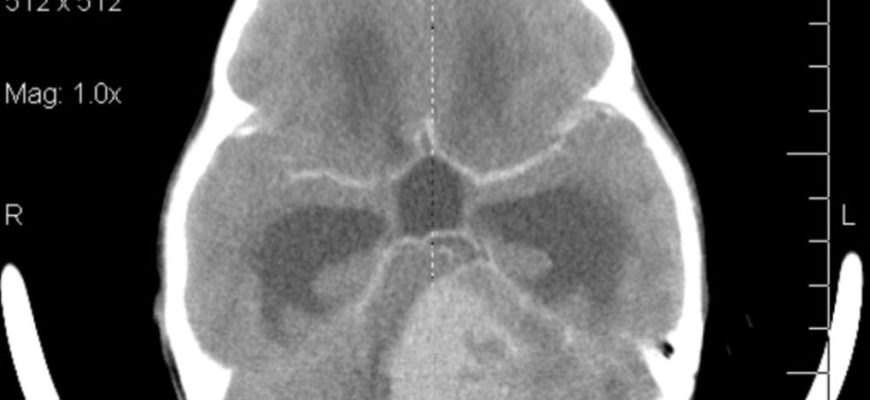

Медуллобластомы обычно поражают заполненную жидкостью четвертую полость (желудочек) головного мозга. Головной мозг имеет четыре полости, называемые камерами, которые заполнены спинномозговой жидкостью (ЦСЖ) и соединены каналами, по которым эта жидкость циркулирует. Поскольку опухоль часто заполняет четвертый желудочек, нарушается циркуляция спинномозговой жидкости, что приводит к гидроцефалии. Гидроцефалия — это состояние, при котором накопление избыточного количества спинномозговой жидкости в головном мозге вызывает различные симптомы, в том числе повторяющуюся, часто сильную рвоту, сонливость и головные боли, которые часто возникают утром и уменьшаются в течение дня. Дополнительные симптомы могут включать:

Основным специализированным методом визуализации, используемым в диагностике медуллобластомы, является магнитно-резонансная томография (МРТ) головного и спинного мозга. МРТ использует магнитные поля и радиоволны для создания подробных изображений поперечных сечений органов и тканей. Эксперты отмечают, что при наличии МРТ предпочтительнее компьютерной томографии (КТ) в качестве диагностического инструмента для медуллобластом, поскольку он может дать более точное представление о распространении опухоли, возможной инвазии мозговых оболочек и поражении позвоночника. МРТ проводится до и после внутривенного введения контрастного вещества на основе гадолиния. Контрастное вещество заставляет опухоль появляться на экране в виде светлой массы (намного ярче, чем окружающая ткань). Когда МРТ недоступна, может быть выполнена компьютерная томография. Компьютерная томография использует компьютер и рентгеновские лучи для создания изображения внутренних структур.